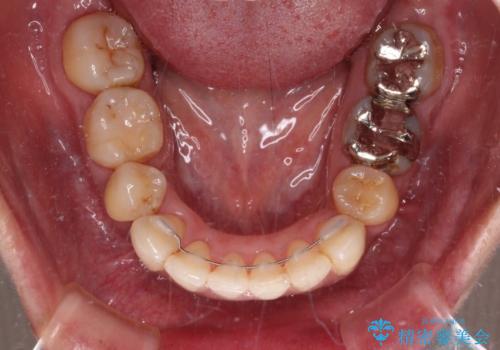

口元を引っ込めることができたため、口を閉じるときに力が入っていて皺のよっていた顎先も、スムーズに閉じられるようになったことで力がかからなくなりました。

変色して気になっていた前歯も、オールセラミッククラウンで自然な色合いにすることができました。